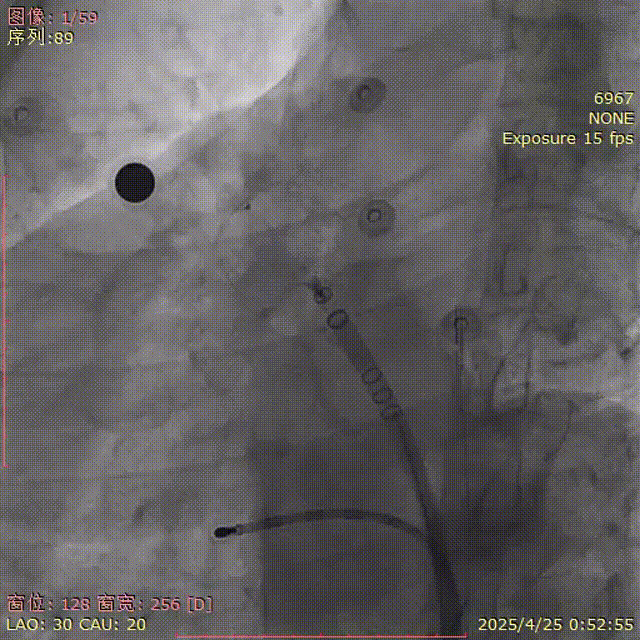

肩位造影

LAO 30° CRA 20°

肝位造影

LAO 30° CAU 20°

行左心耳造影,测量心耳大小,选择合适的封堵器